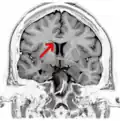

Coronal T2 (grey scale inverted) MRI of the brain at the level of the caudate nuclei emphasizing corpus callosum

Coronal T2 (grey scale inverted) MRI of the brain at the level of the caudate nuclei emphasizing corpus callosum -